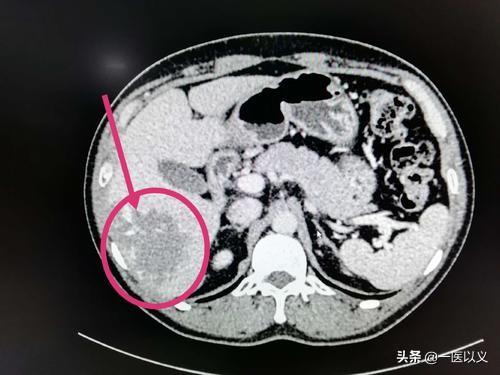

- La tomodensitométrie du foie peut montrer plus clairement le nombre et la taille des hémangiomes hépatiques, avec des résultats supérieurs à ceux de l'échographie du foie.Pour les patients chez qui un hémangiome hépatique a été détecté après une échographie du foie, un examen tomodensitométrique complémentaire du foie peut être effectué pour préciser le nombre, la taille et la localisation des hémangiomes, etc.

L'image ci-dessus est une image tomodensitométrique d'un hémangiome hépatique avec une ombre de faible densité dans le lobe droit avec des bords clairs et un rehaussement progressif du bord vers le centre après le rehaussement.